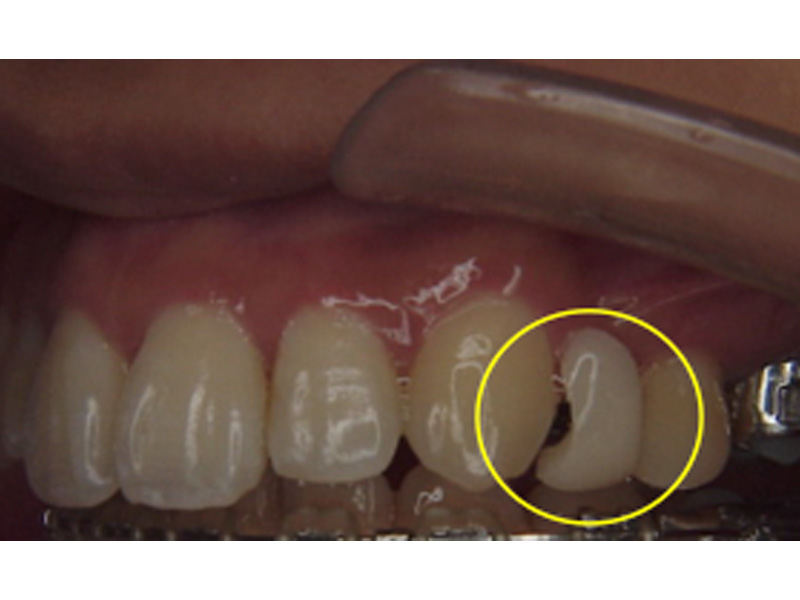

ダミー歯

歯の突出やデコボコの程度が大きい場合、歯を抜いて矯正治療をすることがあります。箇所によっては、その隙間が見た目に気になると感じることがあるかもしれません。

そのような場合、その部分の矯正装置に人工歯を組み込むことができます。飾りなので、咬むのに使うのは厳禁ですが、見た目は十分にカバーされます。唇側・舌側のいずれでも、可能です。